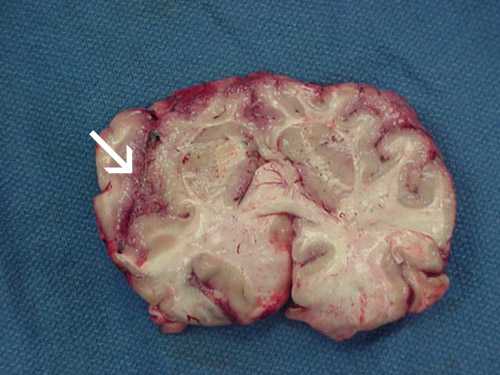

Photos of Naegleria fowleri

These photos of Naegleria fowleri in a variety of forms are presented to aid in laboratory diagnosis. Please be aware that these photographs are intended to aid in laboratory diagnosis and may be disturbing to some viewers.